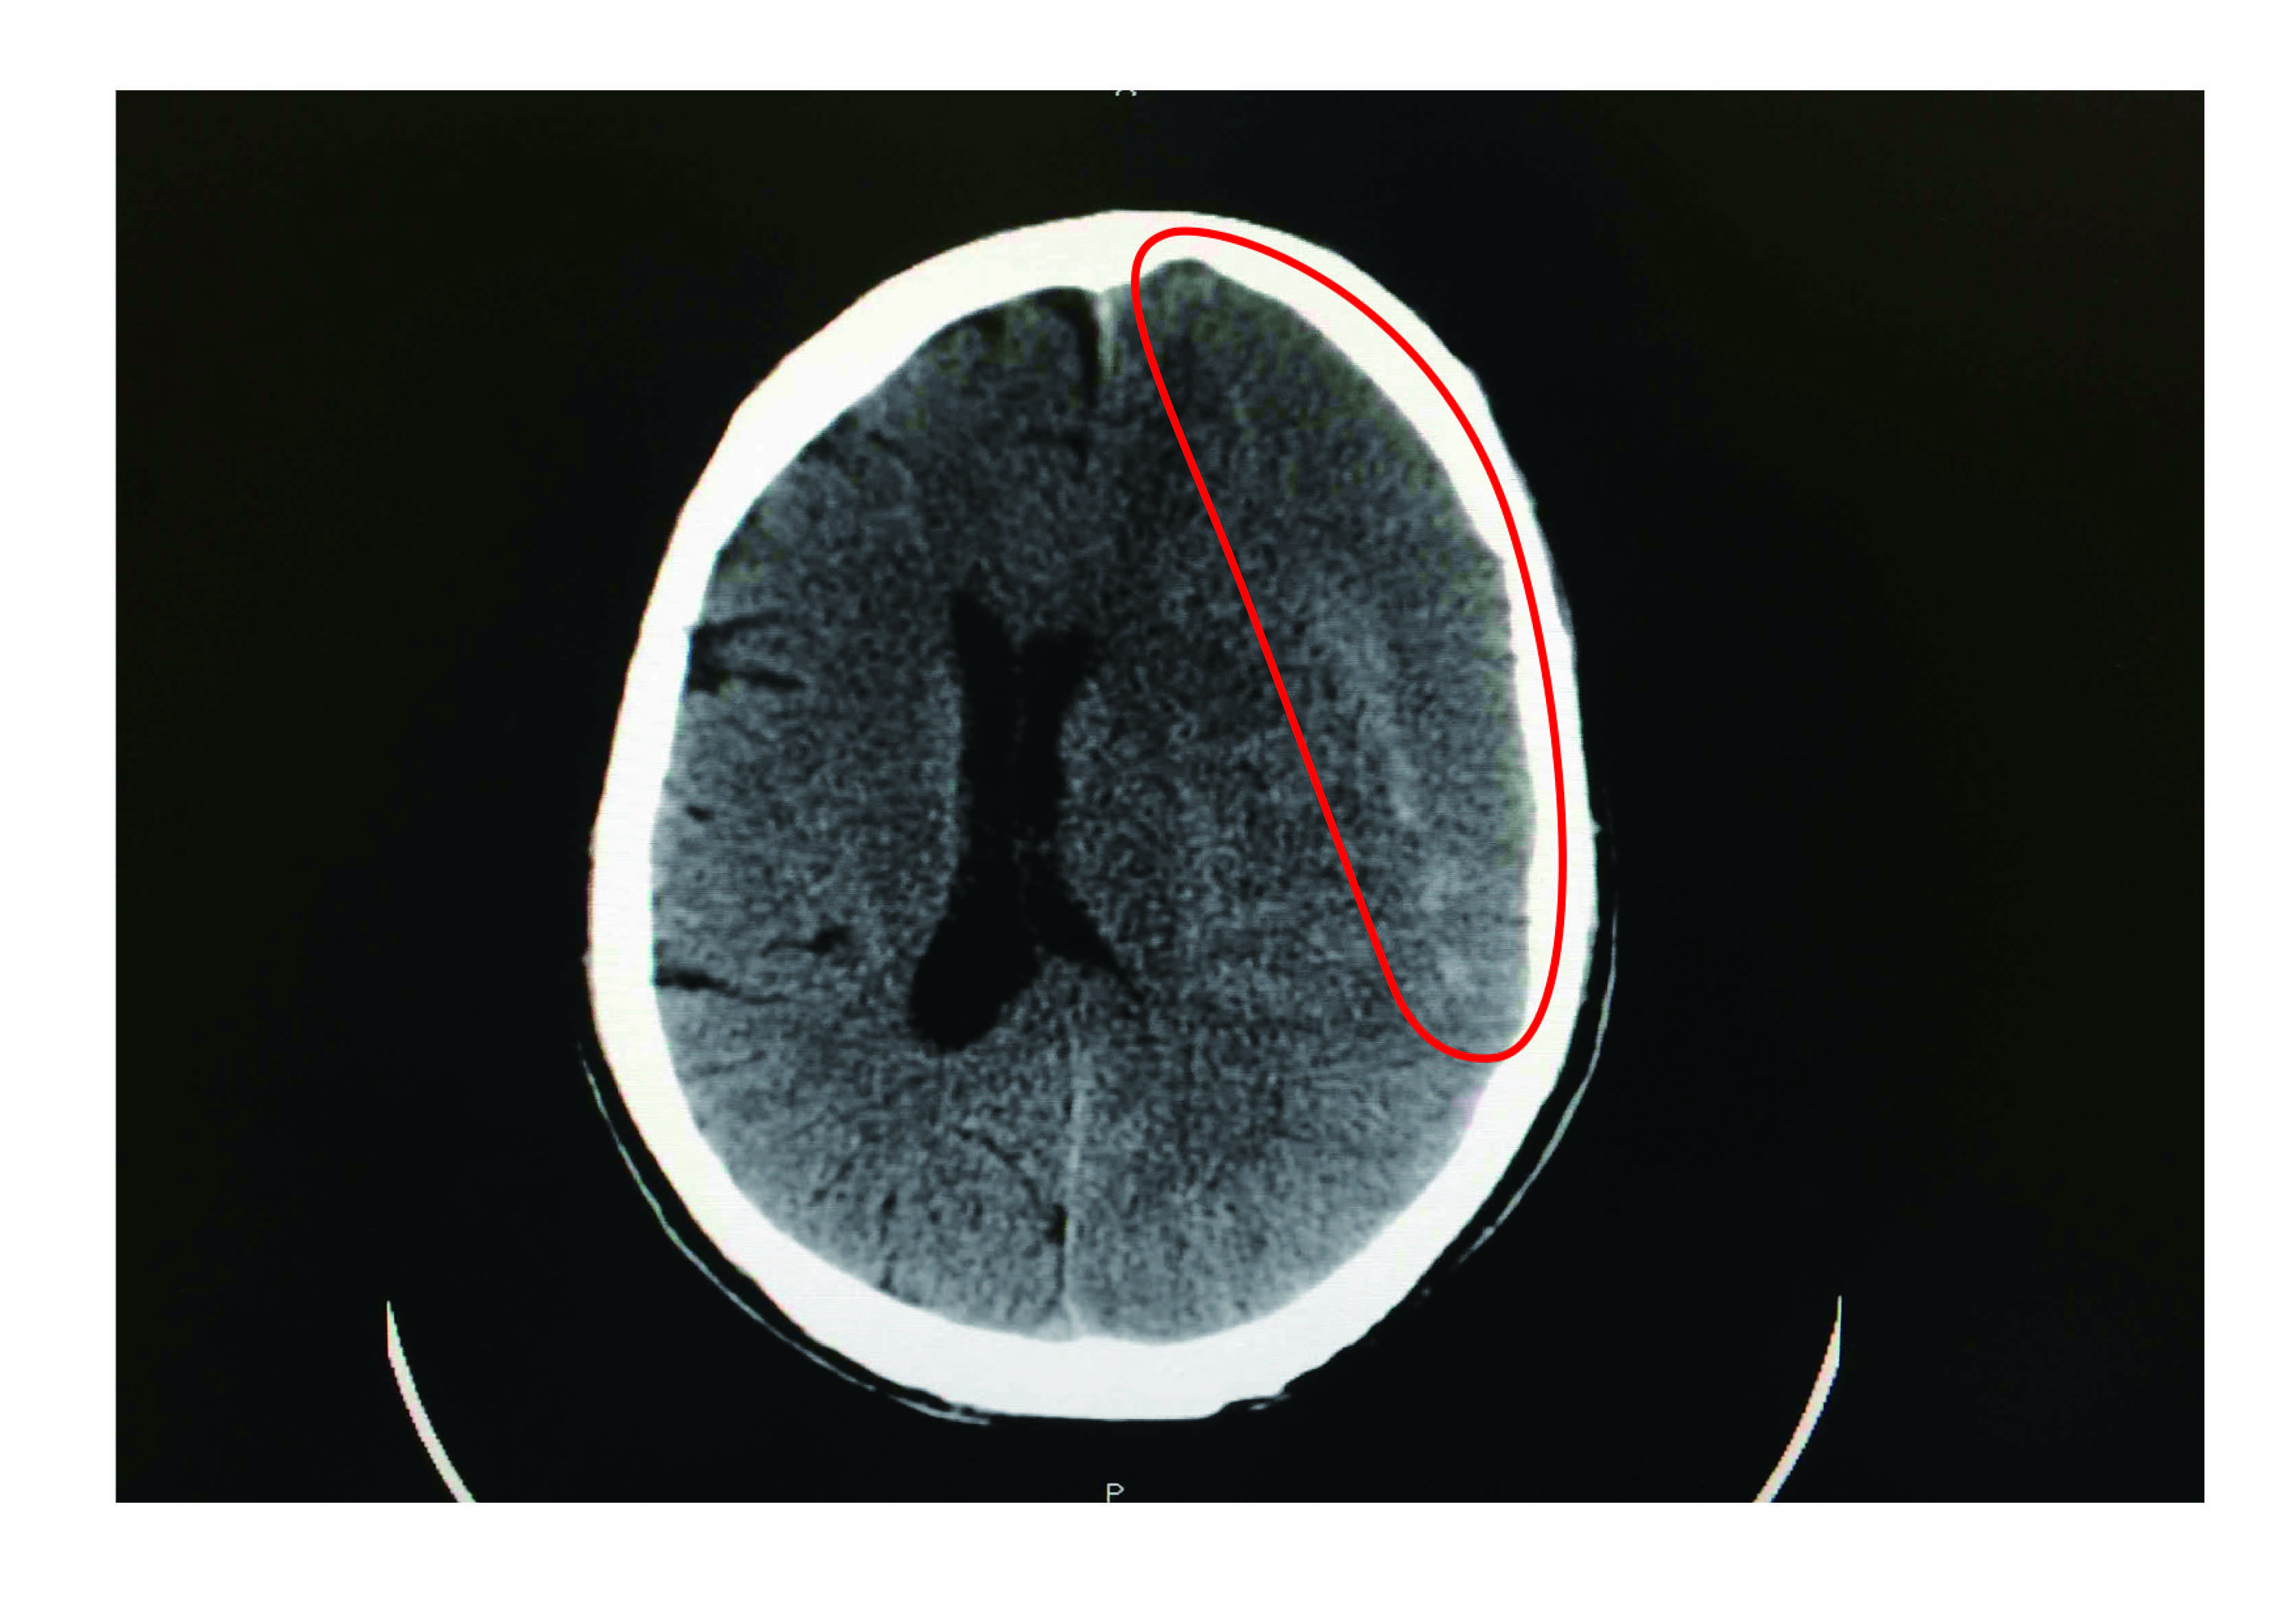

【大紀元2016年12月13日訊】65歲廖姓男子日前工作時遭木板砸頭,當下不以為意,隔天起床卻出現右側手腳明顯無力,經就醫確診為慢性硬腦膜下出血,經緊急手術引流後才逐漸康復。

此外,求診患者中,半數是年長者。由於初期症狀不明顯,但當顱內滲血逐漸形成血腫塊導致顱內壓力增加壓迫到腦組織時,病症小到頭痛、嘔吐;大至偏癱、昏迷、意識不清甚至危及生命。

林牧熹說,腦部受撞擊後,可能在硬腦膜下腔形成血腫,如果血腫小、沒明顯症狀,正常身體會慢慢吸收,但有些人可能因體質或年紀大伴有腦萎縮等原因,身體無法被完全吸收血腫,隨時間增長,血腫越來越嚴重即形成慢性硬腦膜下腔出血,逐漸壓迫到大腦。(轉自中央社)